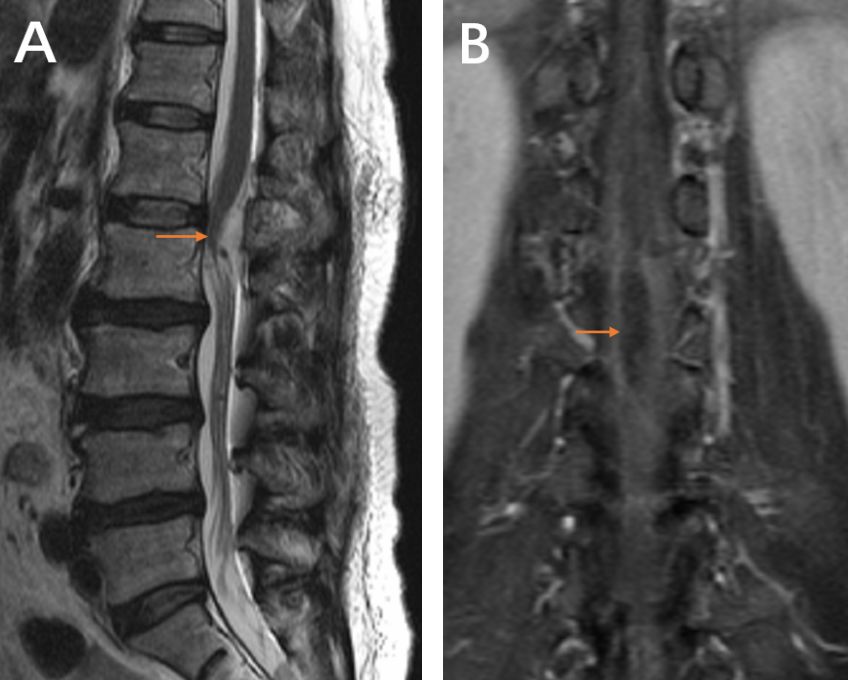

患者术后疼痛缓解,第2天下床活动。术后5天复查腰MRI(图4)未见肿瘤残留,左侧椎旁肌肉无明显损伤。术后病理(图5)提示(L1-2椎管内)神经鞘瘤。

图4. 术后腰椎增强磁共振及CT:A.B.C.术后增强扫描未见异常强化征象。D.术后VRT重建见腰1/2左侧微小骨窗,左侧关节突无破坏。